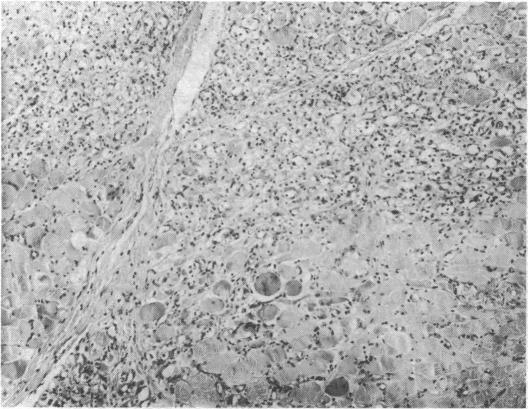

Of five chronic alcoholics with acute skeletal muscle necrosis (rhabdomyolysis) three developed acute heart failure with disturbances of rhythm and conduction. Symptoms came on abruptly after a period of intensified drinking. Myocardial infarction, thiamine deficiency, and cobalt intoxication were excluded. Probably the whole spectrum of muscle disease in chronic alcoholism may be commoner than has been suspected.

在五名患有急性骨骼肌坏死(横纹肌溶解症)的慢性酗酒者中,有三人出现了伴有节律和传导紊乱的急性心力衰竭。症状在一段饮酒加剧期后突然出现。排除了心肌梗死、硫胺素缺乏和钴中毒。慢性酒精中毒中肌肉疾病的整个范围可能比人们怀疑的更为常见。